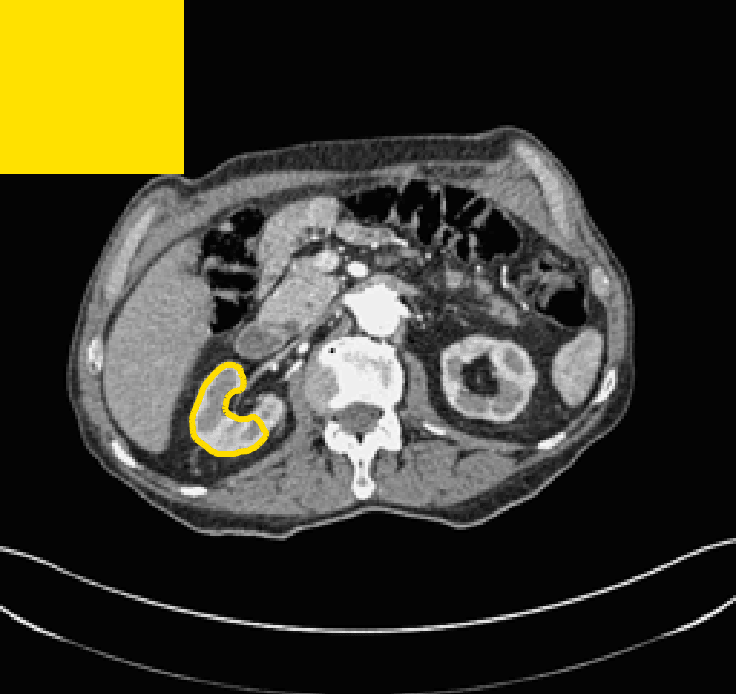

The motivation for this work comes from observing contradictions in using piecewise-constant intensity fitting terms in selective segmentation. Whilst good results are possible with this approach, the exceptional cases lead to severe limitations in practice. This is quite common in medical imaging as demonstrated in Fig. 1, where the target foreground has a low intensity. Given that the corresponding background includes large regions of low intensity, the optimal average intensities for this segmentation problem are and . For cases where , we see that by (1), almost everywhere in the domain . This means that it is very difficult to achieve an adequate result, without an over-reliance on the user input or parameter selection.

for and as defined in (33). This is consistent with respect to the intensities of the observed object and the concept of selective segmentation. In Fig. 3 we see the difference between CV and the proposed fitting terms for given user input on a CT image. For the CT image, the CV fitting terms are near 0 within the target region. This is despite there being a distinct homogeneous area with good contrast on the boundary. This illustrates the problem we are aiming to overcome. With the proposed fitting term this phenomenon should be avoided in cases like this. By defining as in (33) there is no contradiction if the foreground and background intensities of the target region are similar.